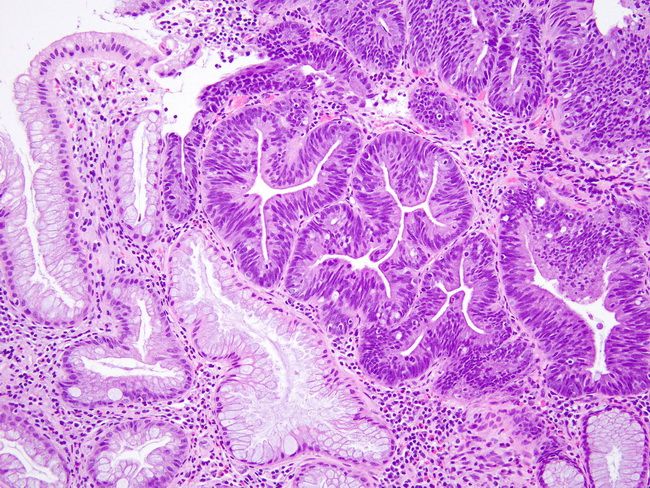

Аденома 2 5

Аденома 2 5 106 фотографий